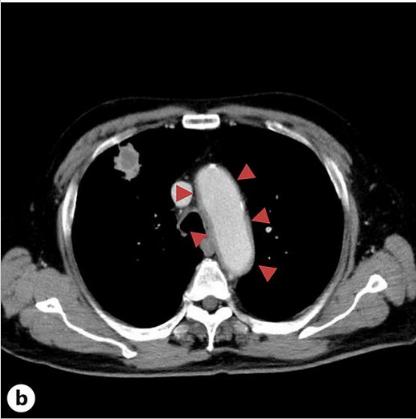

患者接受了卡铂/依托泊苷/杜伐单抗(Dur)和PEG-G-CSF的全剂量组合治疗,重点是剂量强度。在施用PEG-G-CSF后10天施用第四剂冠状病毒疫苗。在PEG-G-CSF给药后的第12天,出现38℃的发热和右耳疼痛,这种情况没有改善,并在第17天就诊。血液检查显示炎症反应明显升高,白细胞计数为15600/μL,C-反应蛋白为33.9 mg/dL,白细胞介素6 (IL-6)水平为114 pg/mL。然而,对整个躯干和头部的物理检查和简单的CT未能检测出发热源或炎症反应升高的原因(图一a)。虽然患者没有出现FN,但不能排除细菌感染的可能性,立即住院并使用了氨苄西林/舒巴坦。第二天对整个躯干进行的CE-CT显示主动脉弓降胸主动脉周围的脂肪组织密度增加,提示主动脉炎(图一b)。患者抗中性粒细胞胞浆抗体和其他自身抗体检测呈阴性。有乙型/丙型肝炎病毒(HBV/丙型肝炎病毒)感染史,入院后有退热趋势,并接受过ICIs治疗。因此,在没有全身皮质类固醇治疗的情况下,仅用解热镇痛药并进行了仔细的随访。第20天,患者体温改善至36°C,右耳疼痛和炎症反应逐渐改善,第33天的对比CT显示主动脉周围炎症表现改善(图一C,2)。那时血清IL-6水平降至8.7 pg/mL。由于免疫相关不良事件的可能性仍然存在,卡铂/依托泊苷的剂量减少到80%,Dur在第二个疗程的化疗中被停用。患者的病情进展顺利,除了白细胞计数略有下降。剂量减少的卡铂/依托泊苷以4周的间隔继续治疗,患者的进展良好,没有主动脉炎发作的迹象。

图1、患者的CT图像。A、PEG-G-CSF给药后第17天拍摄的胸部平面CT图像。此图像没有显示主动脉周围阴影增加。B、在PEG-G-CSF给药的第18天获得的胸部对比增强(CE)-CT扫描。此图显示主动脉周围阴影增加,提示主动脉炎。C、在PEG-G-CSF给药的第33天进行胸部CE-CT扫描。如图中的红色三角形所示,主动脉周围的阴影比图B中所示的要小